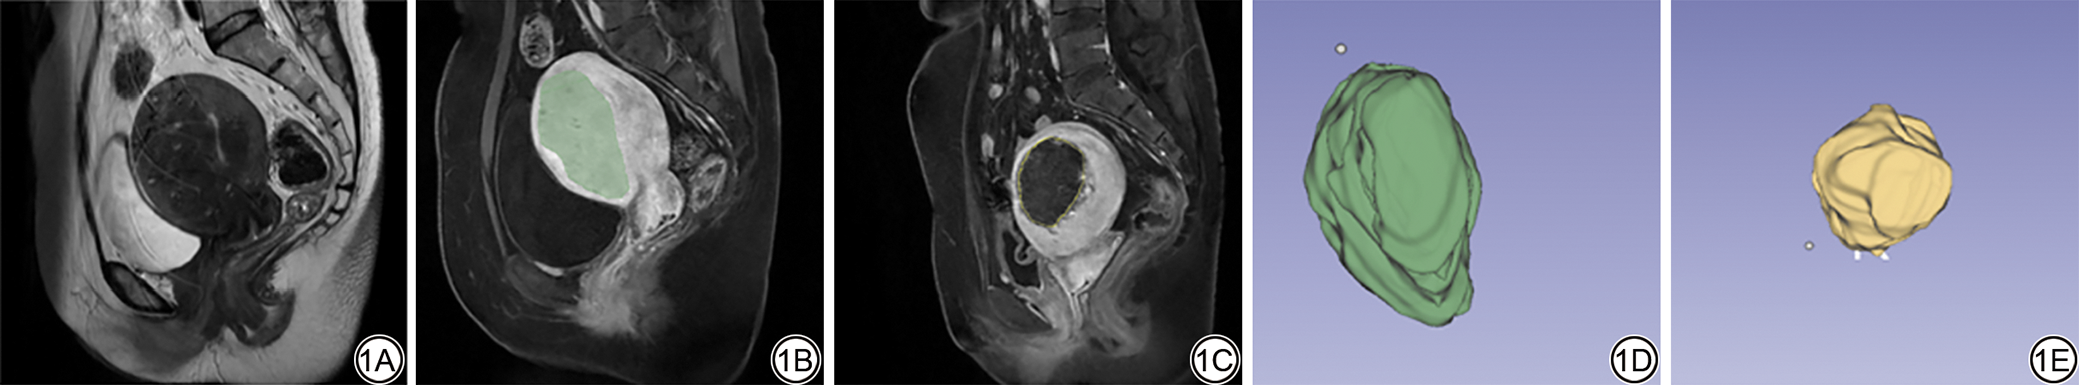

图2  女,37岁,子宫腺肌病病灶影像表现。2A:子宫腺肌病病灶在增强磁共振成像上表现为轻度强化;2B:子宫腺肌病病灶在T1WI上表现为边界不清的等信号,与子宫肌层相仿;2C:子宫腺肌病病灶在T2WI上呈边界不清的混杂低信号。

Fig. 2  Female, 37-year-old, representative MRI findings of uterine adenomyosis. 2A: The lesion exhibits mild enhancement on contrast-enhanced MRI; 2B: On T1WI, it appears isointense with indistinct margins, resembling the surrounding myometrium; 2C: On T2WI, the lesion presents as a heterogeneous hypointense area with poorly defined borders.